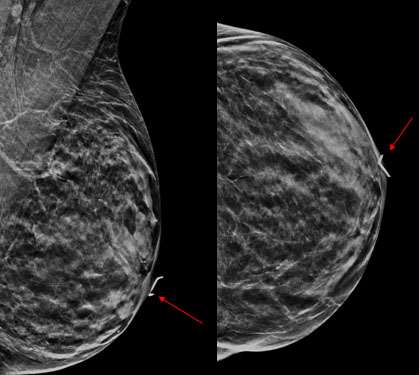

Case: Paget's Disease Figure 2

Figure 2: Targeted ultrasound of the left nipple shows increased vascularity but without a discrete mass.